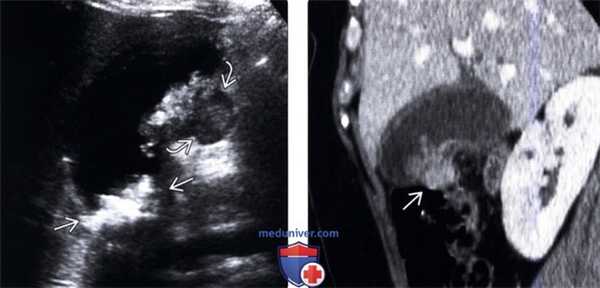

(Левый) У женщины 37 лет с острыми болями в правом верхнем квадранте живота на сагиттальном УЗ срезе желчного пузыря визуализируются отбрасывающие тень конкременты и сладж, а также опухолевидное дольчатое локальное утолщение стенки, прорастающее трансмурально.

(Правый) При КТ с контрастным усилением в режиме мульти планарной реконструкции в той же сагиттальной плоскости определяется полипоидное объемное образование стенки желчного пузыря, накапливающее контраст.